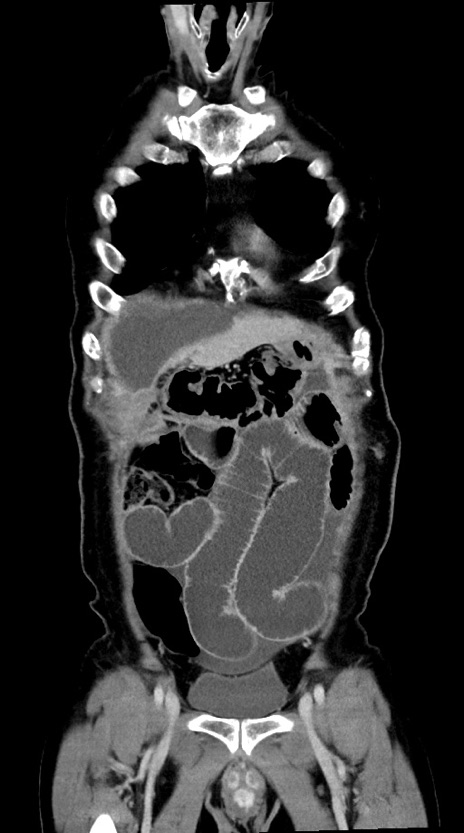

症例28(冠状断像)

【症例】60歳代男性

【主訴】嘔吐

【現病歴】胃癌にて胃全摘後。食思不振が悪化し、夜中に嘔吐することがある。

【既往歴】胃癌、胃全摘、脾摘、胆摘後

【データ】WBC 5900、CRP 10.56